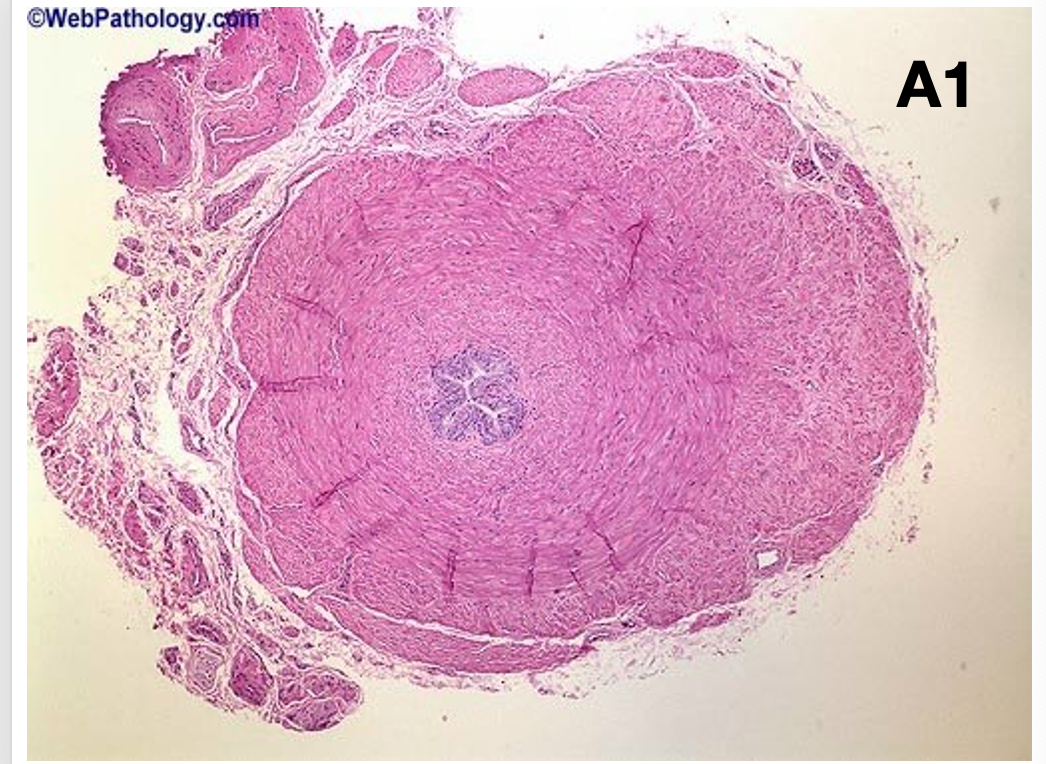

What is this?

Prostate- Fibromuscular glandular

Glands are in white

Pink is fibrous stoma

What are features of spot diagnosis of prostate?